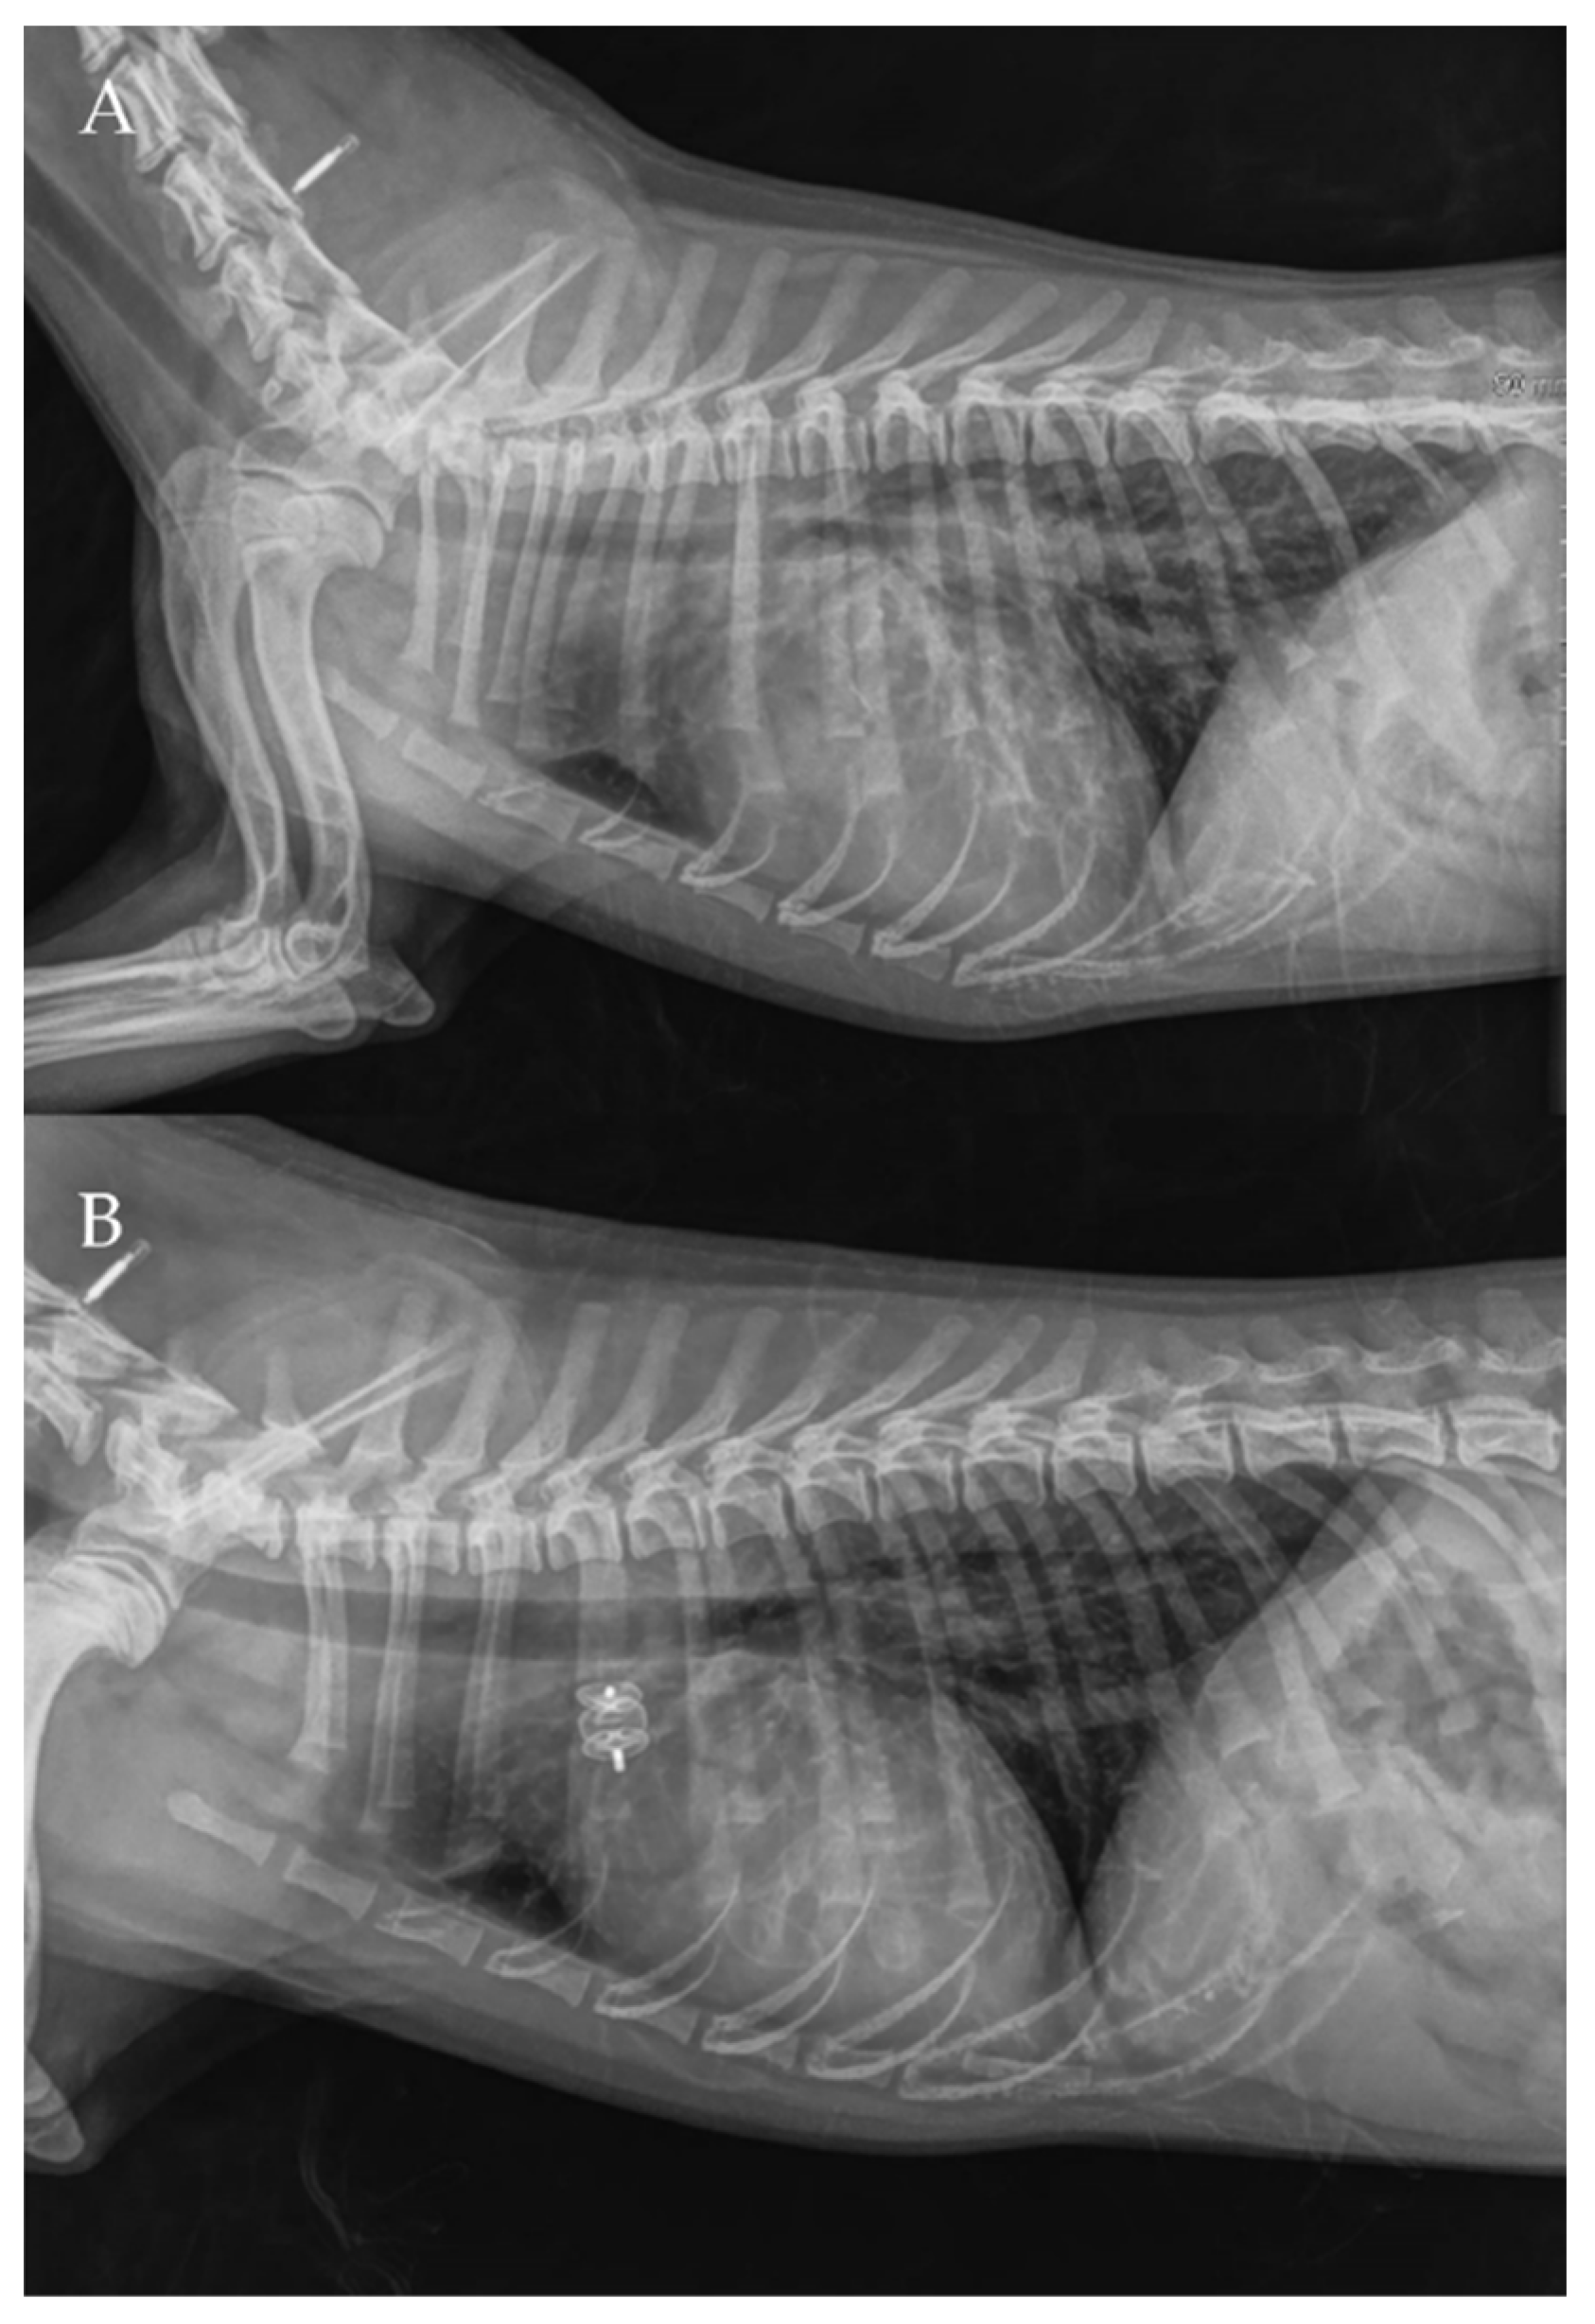

The thoracic radiographs performed before and just after the procedure showed a reduction in the cardiac silhouette as well as significant reduction of the over-circulation vascular pattern for all dogs (Figure 8, Figure 9, Figure 10, Figure 11 and Figure 12).

Figure 10. Pre- (A) and post-procedure (B) right lateral thoracic radiographs of Case 4.